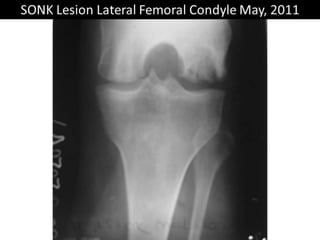

The document presents a detailed case study of a patient with transient osteoporosis of the hip (TOH) and spontaneous osteonecrosis of the knee (SONK) treated at Choithram Hospital & Research Centre in India. Over 20 years, the patient experienced multiple episodes of TOH and SONK with no history of trauma or co-morbidities, resulting in resolutions and recurrences of conditions. The information is intended for orthopedic surgery students and highlights personal experiences and case collections, with a disclaimer regarding content usage and potential controversies.